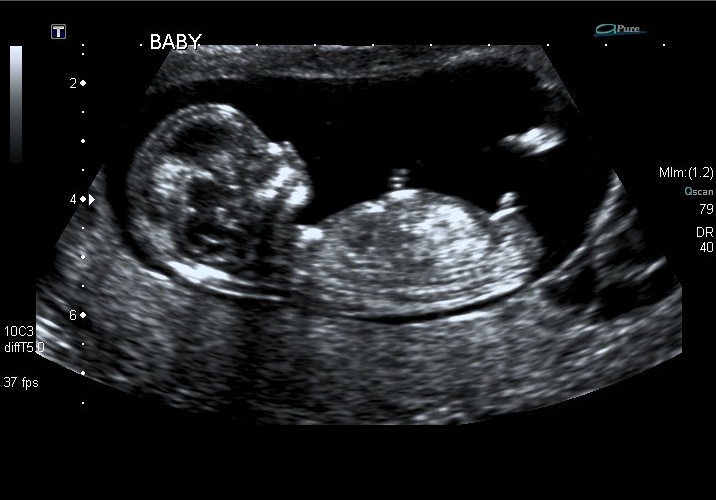

After three rounds of IVF and three FETs we are so excited to complete our family. My 12w6d ultrasound is below, would love some guesses! I see a flat part for girl and a nub above for boy so I can't tell!